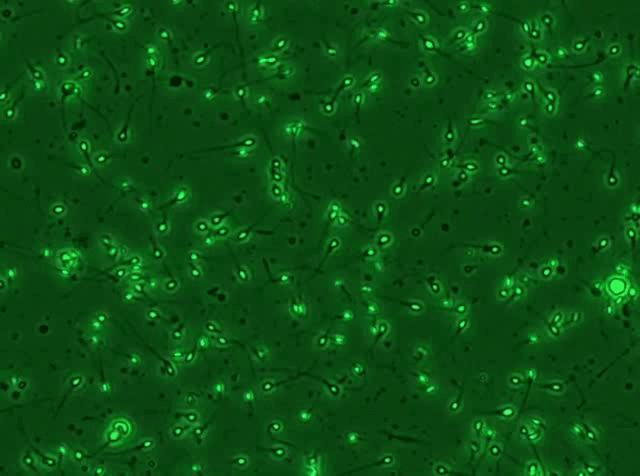

有些人的精子,“精力旺盛”↓

有些人的精子,“不动如山”↓

不要慌!我们先要了解一个基本概念: “精子存活率” ——即在所有计数精子中活精子的比例,主要目的是检测精子的死与活。

活动的精子肯定是活的,就不多说了。但对于那些 不活动的精子,是不是都死了呢?

害,那只能说——这些精子大多都是 “演技派” 。

真正判断精子是生是死,不能光看它动还是不动。

一般实验室里观察到的 不动精子,实际有两种情况:

总而言之,实验室会 运用存活率 这个参数,来看看这些“戏精”的比例,从而 判断精子质量。

尤其是前向运动精子小于40%的精液标本,存活率就非常重要,有助于死精子症和不动精子症的鉴别,进而指导临床治疗和辅助生殖。